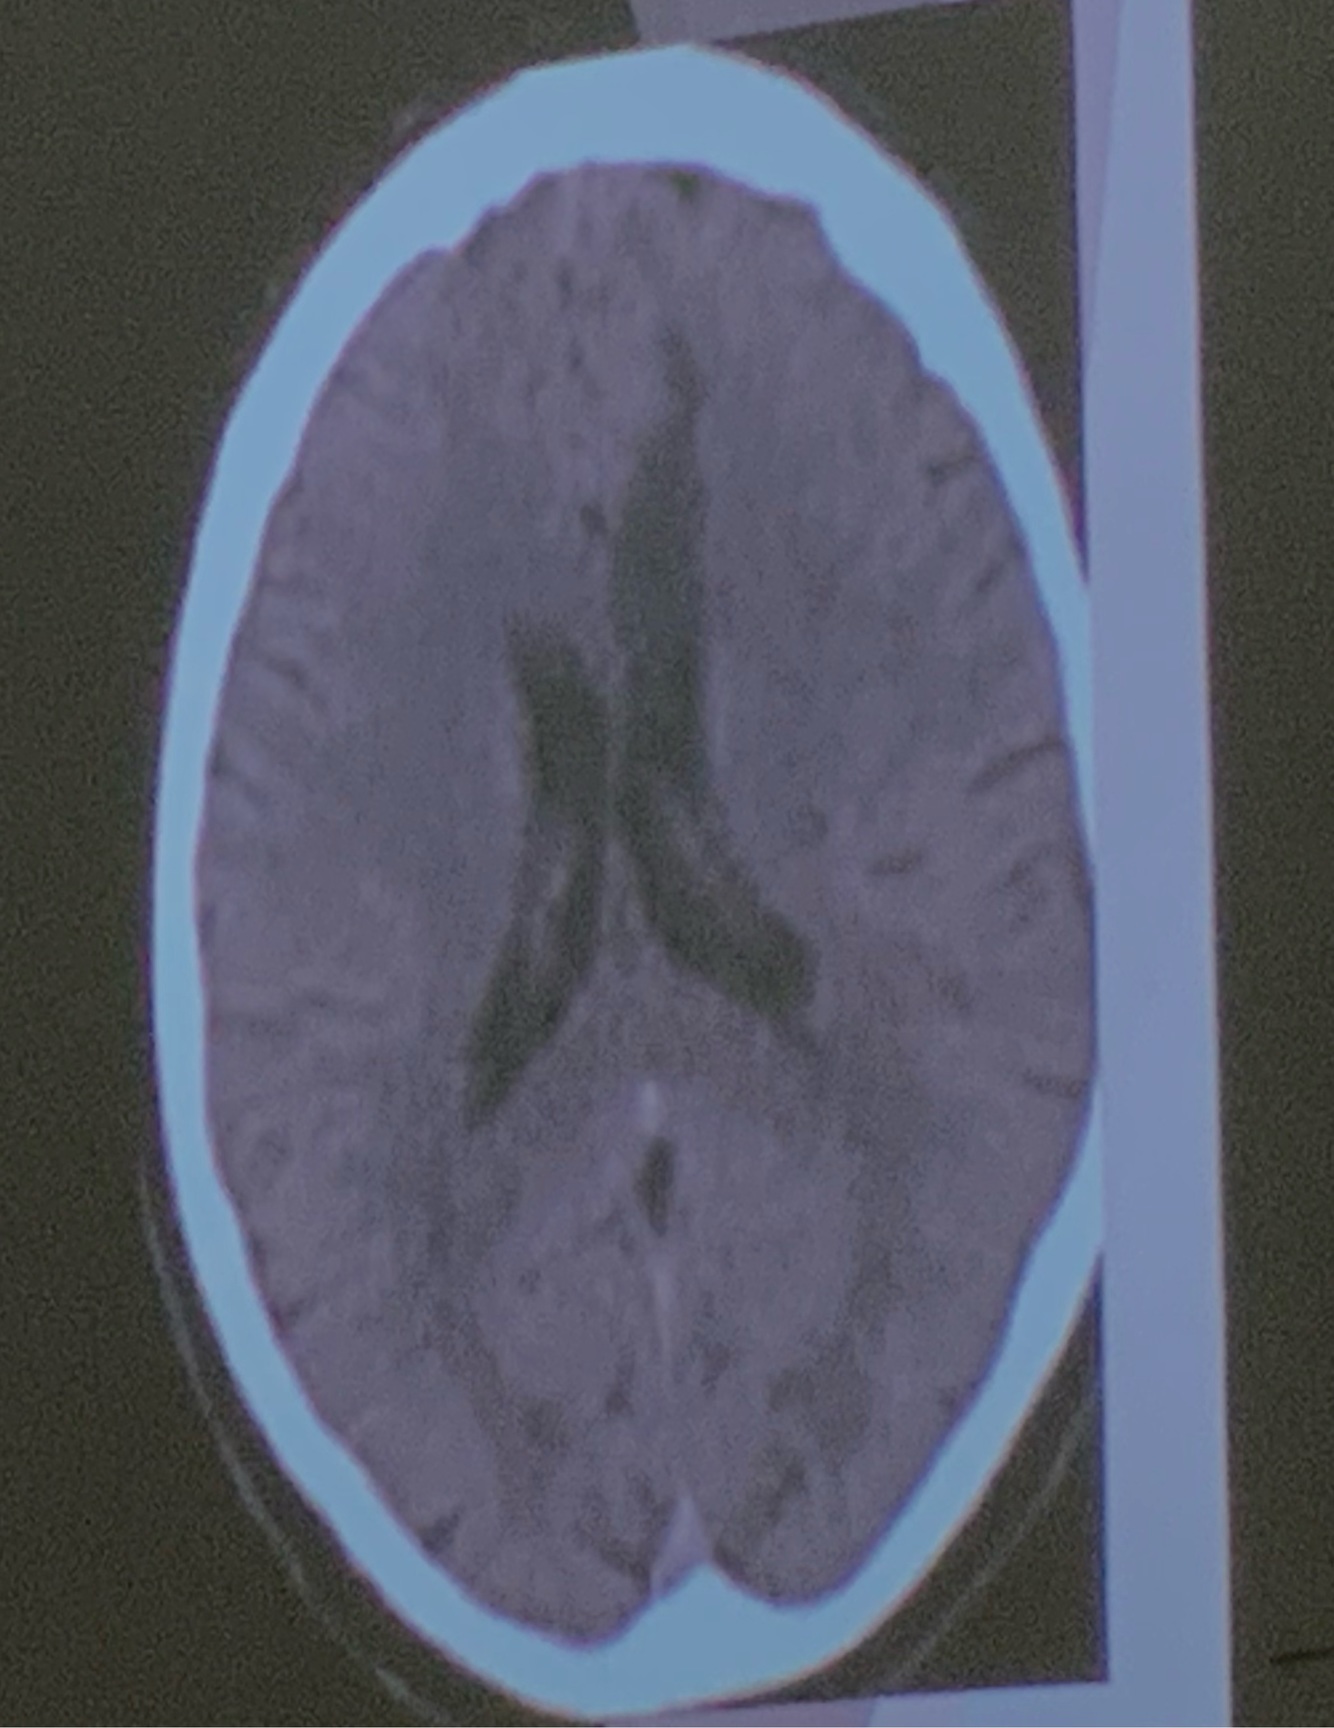

11

Q

Que arteria se encuentra afectada

A

ACA